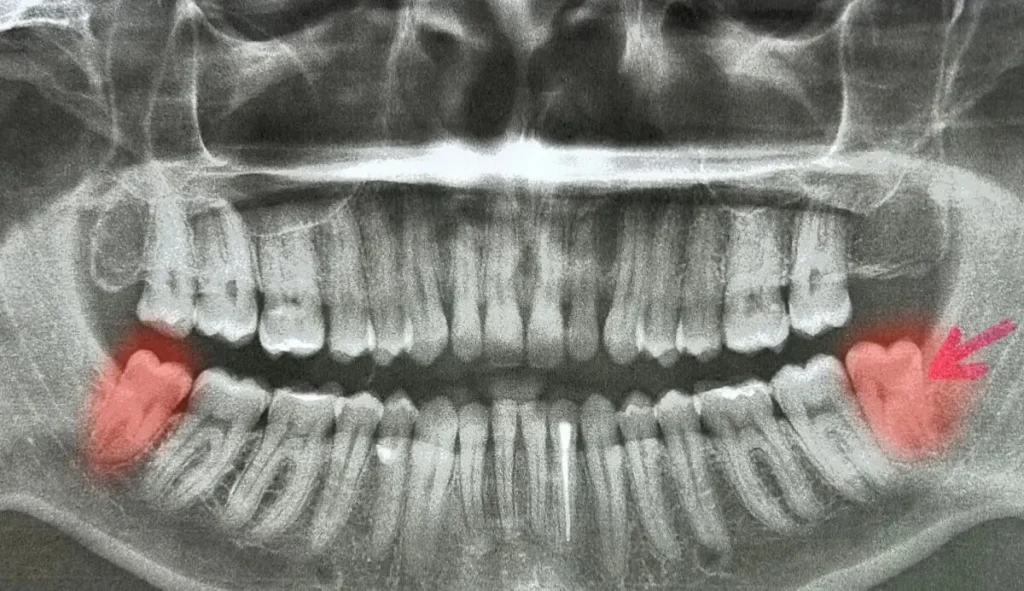

Sebbene molti denti del giudizio emergano senza complicazioni, esistono segnali che indicano la necessità di una valutazione professionale. Dolori persistenti, difficoltà a aprire completamente la bocca, infiammazioni ricorrenti o mal posizionamento dei denti vicini possono richiedere un intervento. La valutazione da parte di un dentista, spesso supportata da radiografie, permette di capire se i denti stanno seguendo un percorso corretto o se il loro posizionamento può creare problemi a lungo termine.